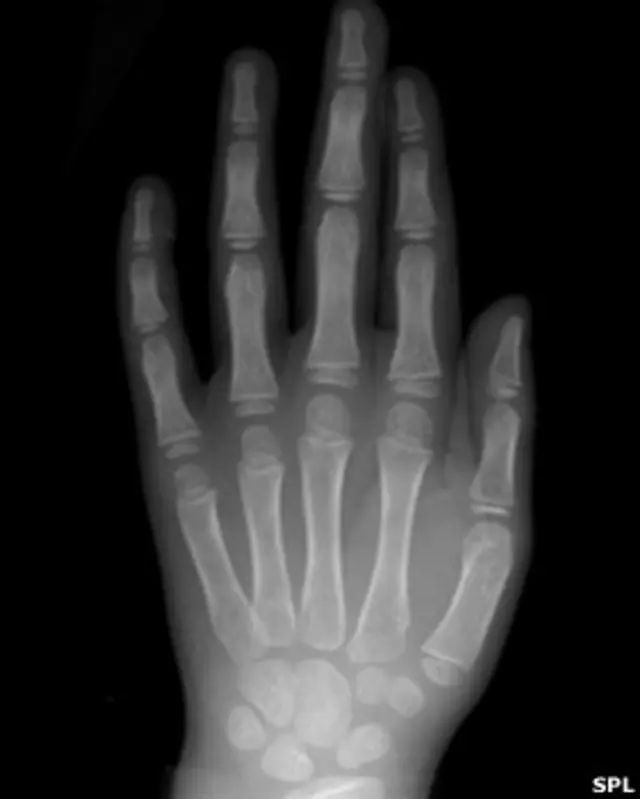

Cerrar el puño incrementa cuatro veces la rigidez de la articulación de la segunda falange del metacarpio, o MCP (los nudillos que se hacen visibles cuando la mano está cerrada).

También duplica la habilidad de las falanges proximales (los huesos de los dedos que se articulan con las coyunturas MCP) de transmitir la fuerza del golpe.